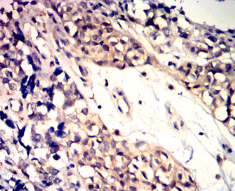

IHC    1/200 - 1/1000